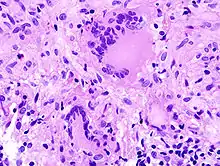

- Zytologisch: Polymorphie, basophiles Cytoplasma, erhöhte Kern/Plasmarelation

- Nukleär: Polymorphie, Polychromasie, Hyperchromasie, Aneuploidie, (vergrößerte) Nukleolen, vermehrt Mitosen, atypische Mitosen, erhöhter Proliferationsindex (Ki-67 = MIB-1).